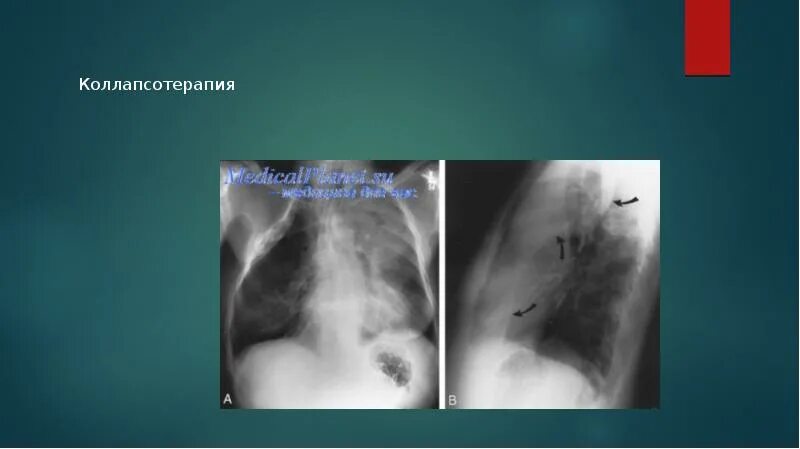

Коллапсотерапия при туберкулезе